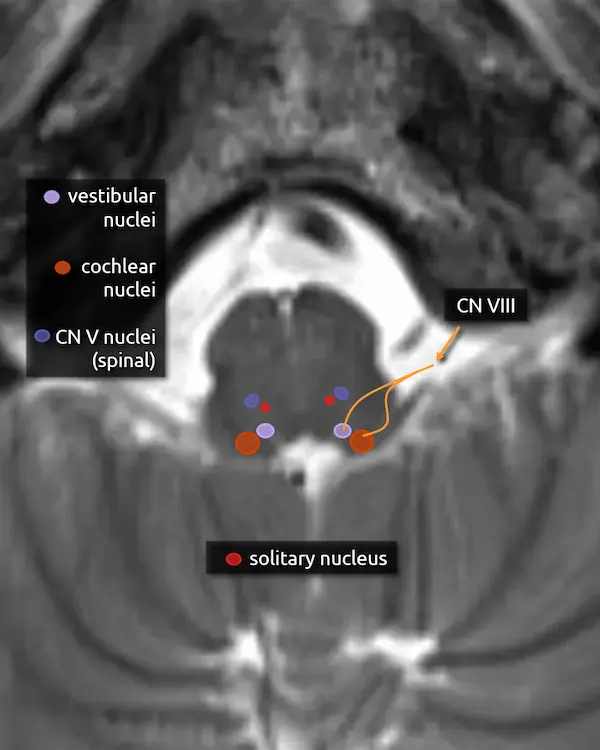

5. Vestibular nuclei (CN VIII)

The vestibular nuclei are a complex of four cell groups located mostly in the dorsal medulla with some extension to the lower pons. The receive information from the inner ear and are responsible for balance, posture, and eye movement in response to head motion.

6. Cochlear nucleus (CN VIII)

The cochlear nuclei are a complex of two cell groups located in the dorsal medulla. They receive information from the inner ear and are responsible for hearing.

7. Vestibulocochlear nerve (CN VIII)

The vestibulocochlear nerve is formed by fibers of the vestibular and cochlear nuclei. It exits the pontomedullary junction lateral and slightly inferior to the facial nerve before entering the internal auditory canal.

The most common mass in the cerebellopontine angle is a vestibular schwannoma, i.e., a schwannoma arising from the vestibular component of CN VIII. Due to its long course through the subarachnoid space, CN VIII is the most commonly involved cranial nerve in superficial siderosis, which manifests as sensorineural hearing loss. The facial nerve, with its similar course, is the second most commonly involved. Similar to the trigeminal and facial nerves, CN VIII may become irritated by nearby blood vessels, manifesting as intermittent vertigo (vestibular paroxysmia).